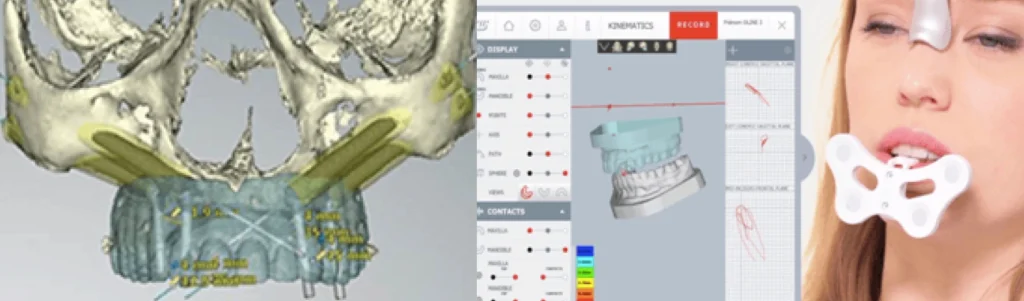

Un scanner osseux 3D de vos mâchoires est réalisé pour déterminer le volume osseux disponible de l’os zygomatique et connaître le décalage antéro-postérieur entre vos mâchoires supérieure et inférieure. Votre occlusion est enregistrée de manière fixe et dynamique pour construire votre future prothèse. Un bilan photographique est nécessaire pour l’évaluation morphologique esthétique de votre visage et de votre sourire de face et de profil.

L’étude implantaire se fait à l’aide d’un logiciel de planification qui intègre le design de la future prothèse qui a été validé d’un point de vue esthétique et fonctionnel pour optimiser le placement des implants. Une fois validé un guide chirurgical en titane imprimé monobloc, est conçu pour reproduire lors de la chirurgie la position virtuelle des implants planifiés gage de plus de précision et de sécurité chirurgicale. C’est un guide à double douille qui stabilise le foret lors du passage dans le maxillaire puis dans le zygoma. L’extension zygomatique du guide est retirée après le forage pour laisser passer l’implant zygomatique guidé.

Conception de la prothèse et positionnement :